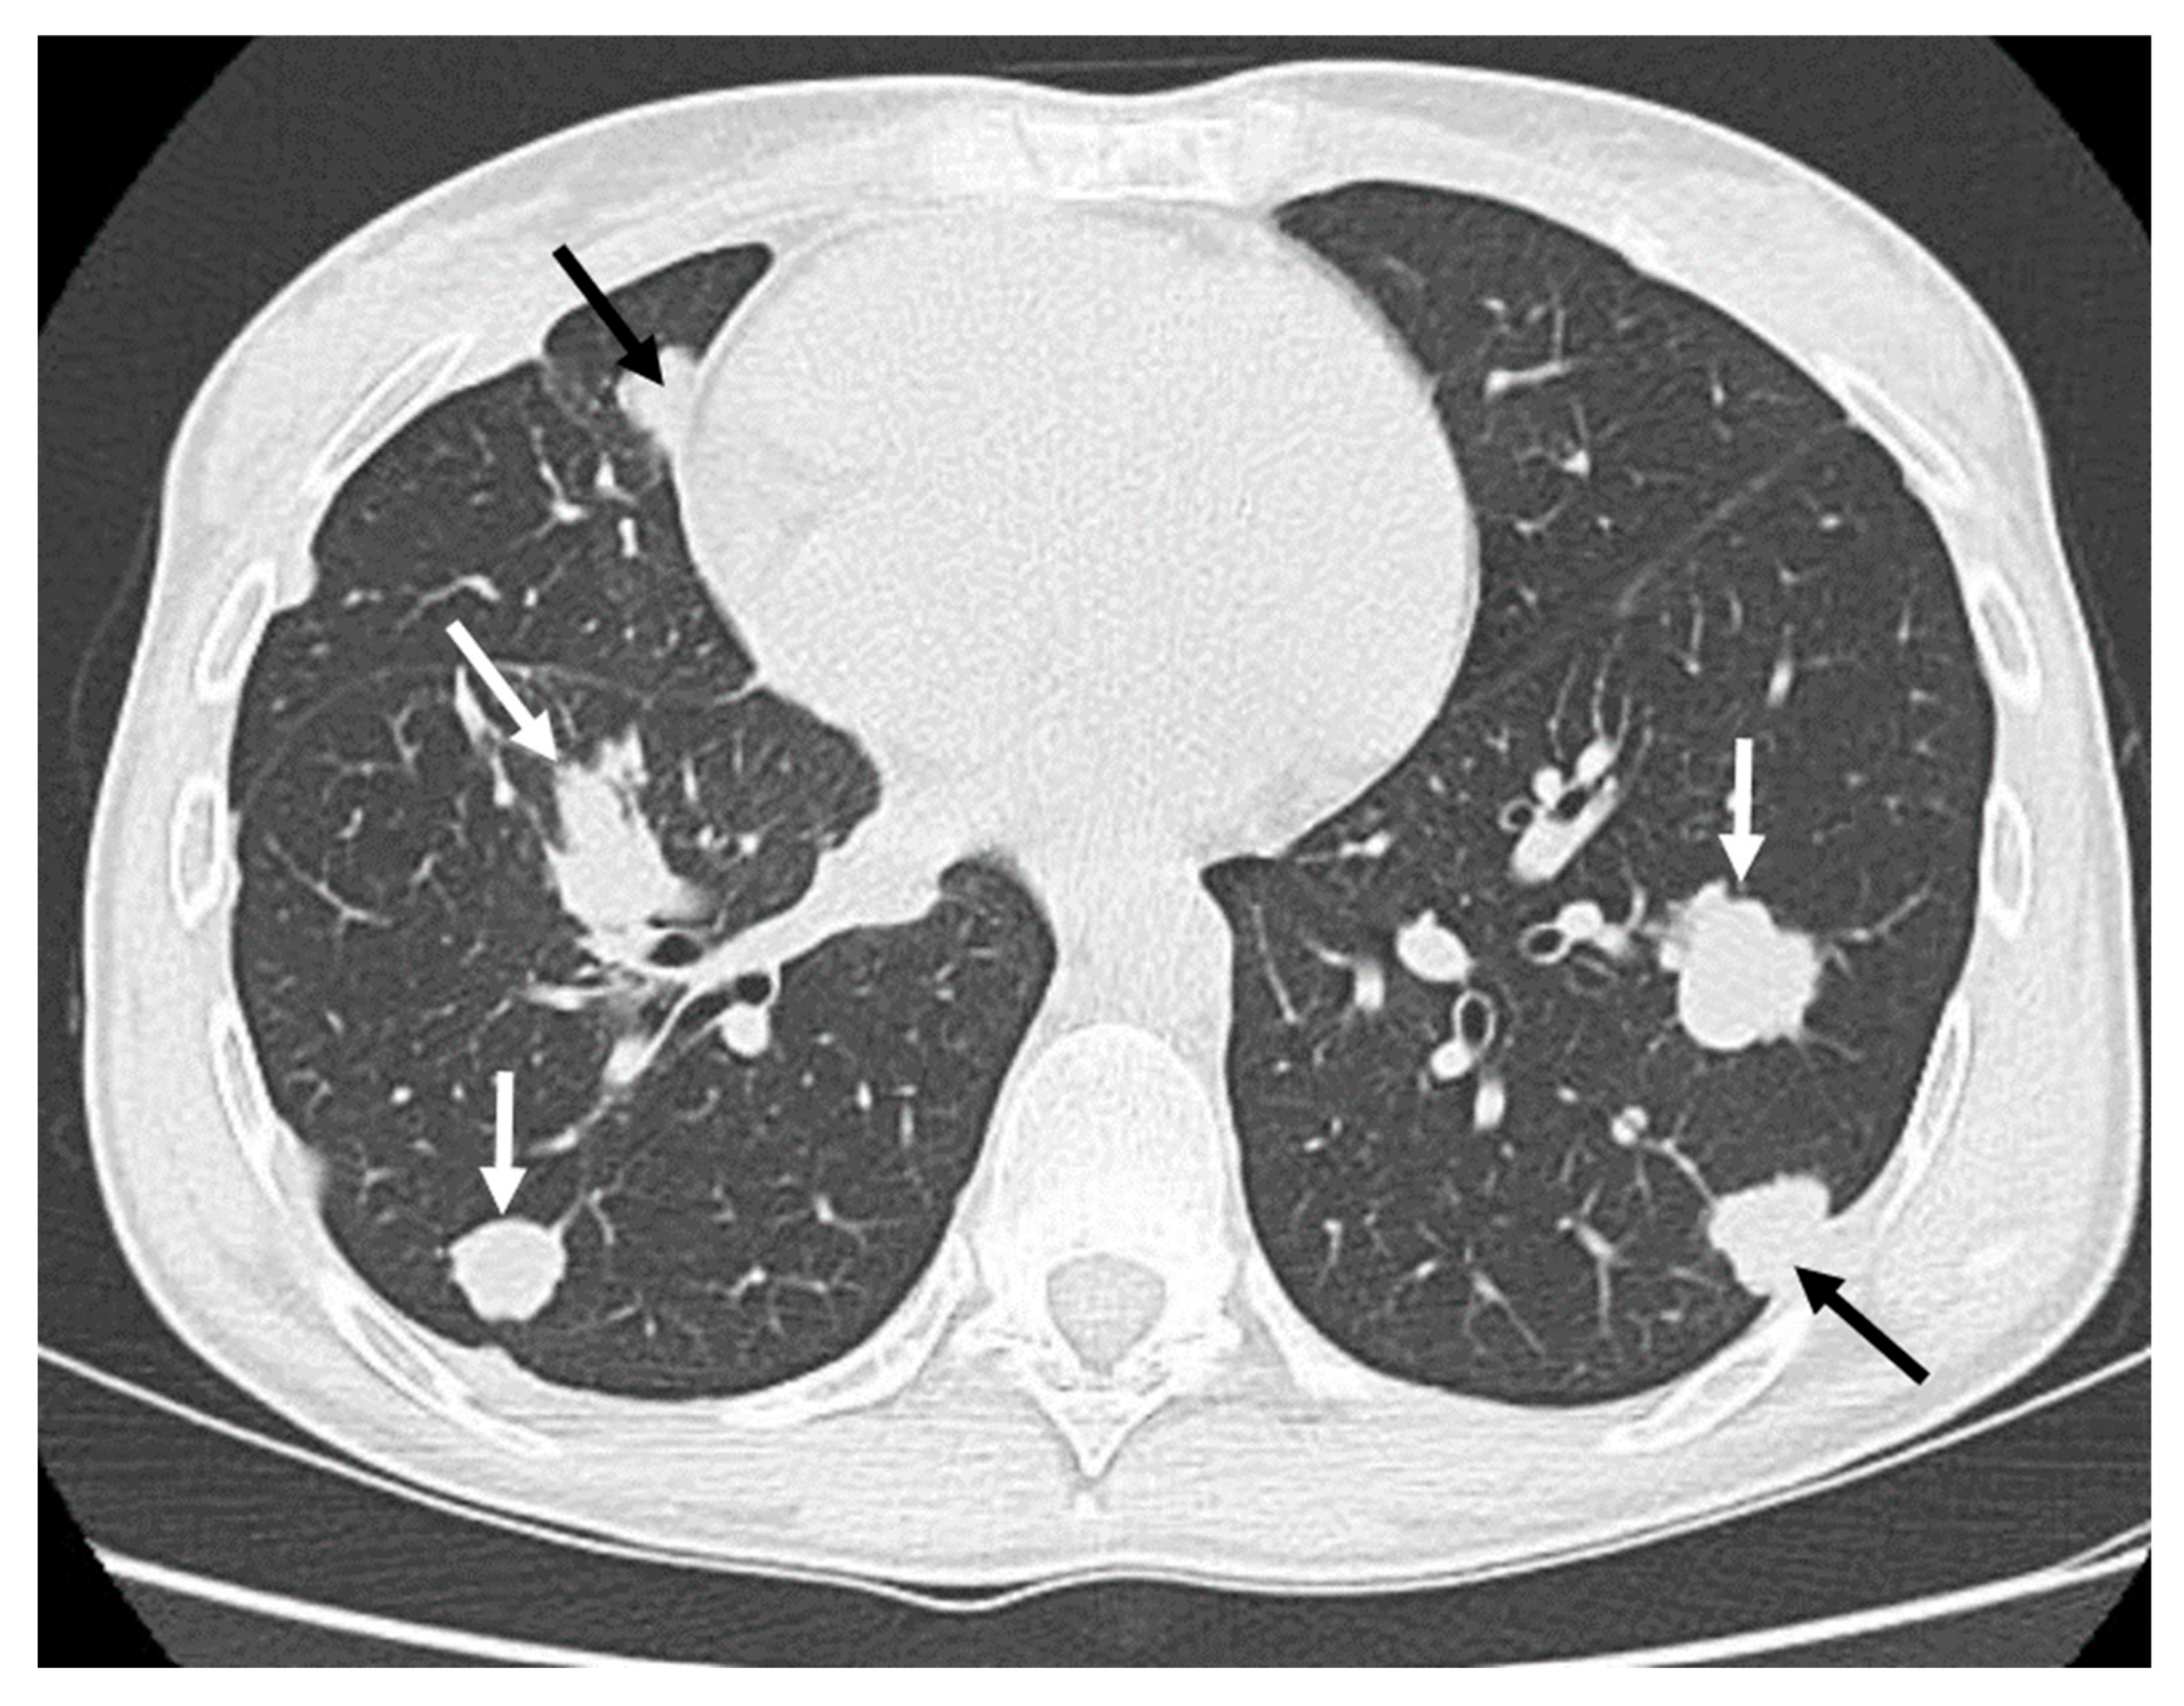

| Extra-intra osseus extension: Intraosseous only (0), intra- and extra-osseous (1) | Intraosseous only (14), Extra-osseous (2) | Intraosseous only (0), extra-osseous (6) | 0.0004 * |

| Vascular invasion: No vascular contact (0), Vascular contact or encasement (1) | No vascular invasion (16), Vascular invasion (0) | No vascular invasion (1), Vascular invasion (5) | 0.0002 * |

| Peritumoral edema: absent or focal (0), diffuse intra and extra-osseous (1) | Absent or focal (14), diffuse (2) | Absent or focal (0), diffuse (6) | 0.0004 * |

| Peritumoral enhancement: absent (0), present (1) | Absent (11), Present (1) | Absent (0), present (5) | 0.001 * |